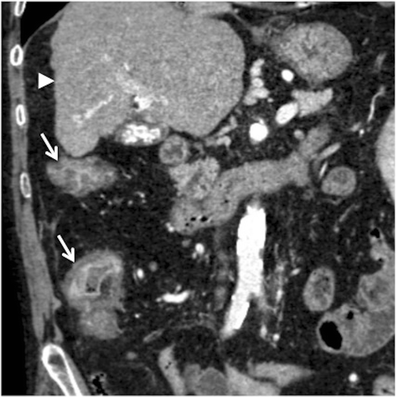

Small bowel wall thickening patterns on ct.

Bowel wall thickening, the main sonographic correlate of bowel disorders, seems at rst glance a very nonspecic sign, which may explain why inexperienced investigators do not feel condent in the sonographic evaluation of the gastrointestinal tract. A/ an inguinal hernia is the protrusion of a small loop of bowel through a weak place in the lower abdominal wall or groin. Bowel wall thickening, the main sonographic correlate of bowel disorders, seems at rst glance a very nonspecic sign, which may explain why inexperienced investigators do not feel condent in the sonographic evaluation of the gastrointestinal tract. Small bowel acute appendicitis bowel wall terminal ileum ileocecal valve.